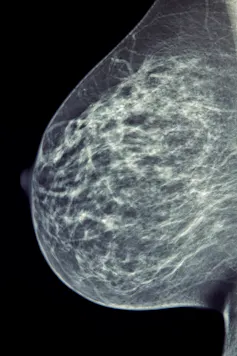

Breast cancer is the most common cancer in the UK. It accounts for 15% of all new cases in the country, and about one in eight women will be diagnosed with it during their lifetime. In the NHS, breast cancer screening routinely includes a mammogram, which is essentially an X-ray of the breast.

Interpreting a mammogram is a complex process normally performed by specially trained radiologists and radiographers. Their skills are vital to the early detection and diagnosis of this cancer. They visually scrutinise batches of mammograms in a session for signs of breast cancer.

But these signs are often ambiguous or hard to see. False negative rates – where cancers are incorrectly diagnosed or missed – are between 20 and 30% for mammography. These are either errors in perception or errors in interpretation, and can be attributed to the sensitivity or specificity of the reader.